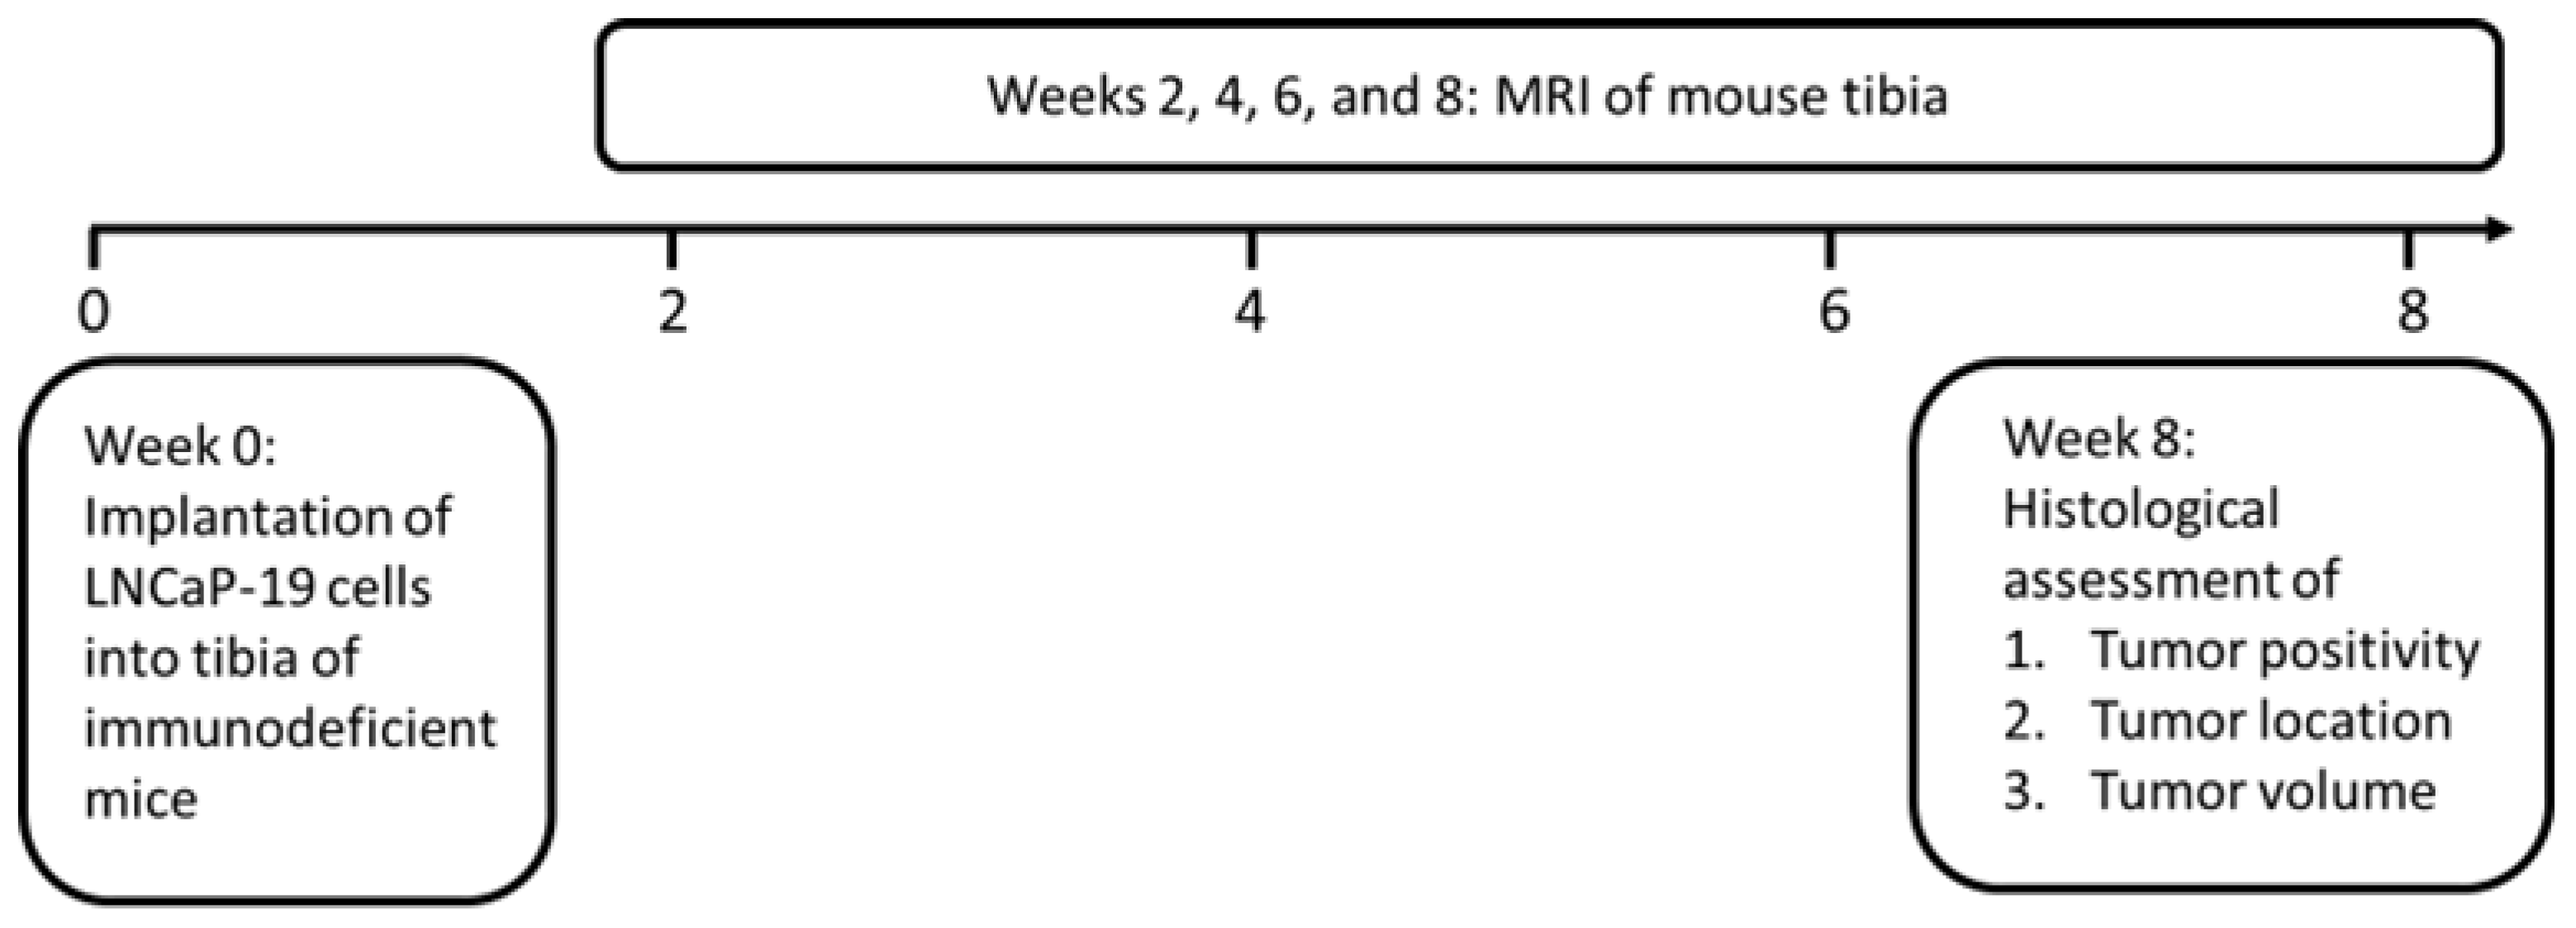

2. Material and Methods

2.2. In Vivo Intratibial Tumors

2.3. Magnetic Resonance Imaging

2.4. Histological Evaluation